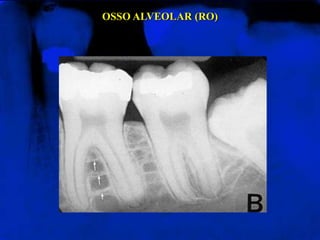

OSSO ALVEOLAR (RO)Chamado também de osso trabecular ou osso esponjoso. Apresenta-se como uma estrutura trabecular radiopaca, limitada por espaços medulares radiolúcidos

OSSO ALVEOLAR (RO)

OSSO ALVEOLAR (RO)Chamadotambém de osso trabecular ou osso esponjoso. Apresenta-se como uma estrutura trabecular radiopaca, limitada por espaços medulares radiolúcidos